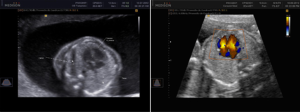

Doppler Obstétrico Feto-Placentario

Doppler Obstétrico Feto-Placentario Evalúa en forma no invasiva el flujo de los vasos sanguíneos de la placenta, del feto, útero y del cordón umbilical, determina cómo